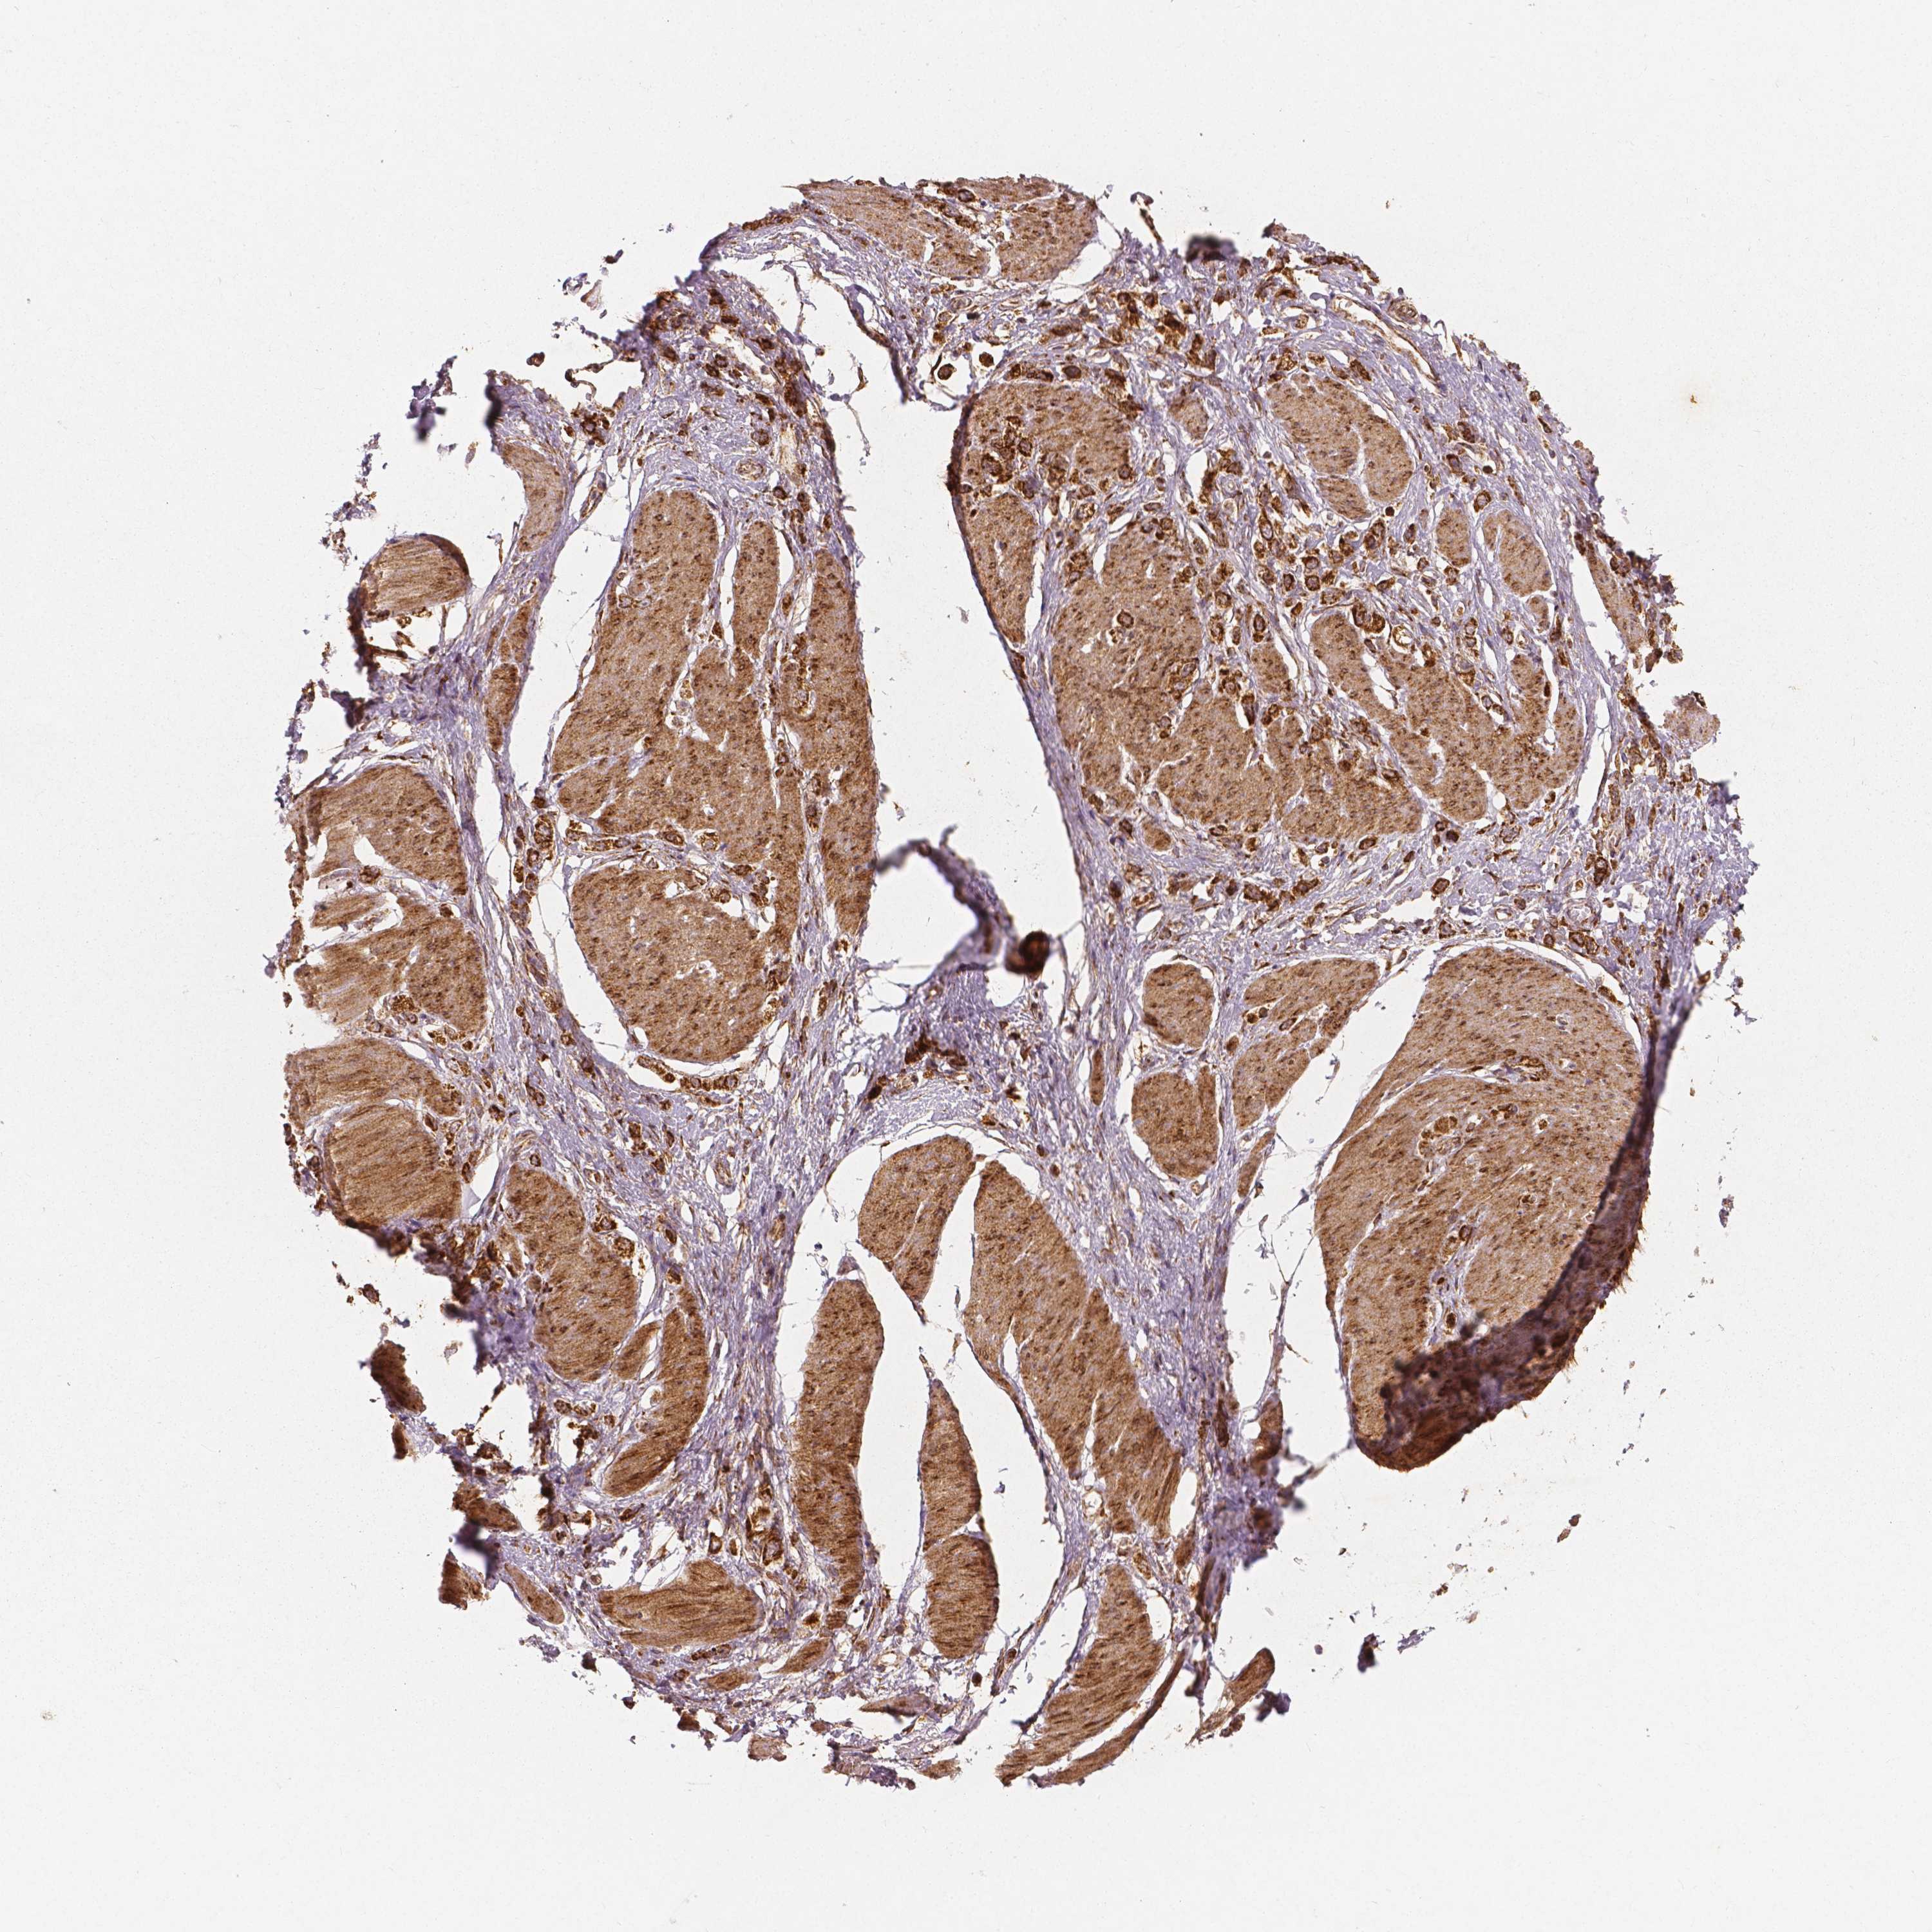

STOMACH CANCER - Protein expressioni

A mouse-over function shows sample information and annotation data. Click on an image to view it in a full screen mode. Samples can be filtered based on level of antibody staining by selecting one or several of the following categories: high, medium, low and not detected. The assay and annotation is described here.

Note that samples used for immunohistochemistry by the Human Protein Atlas do not correspond to samples in the TCGA dataset.

Antibody stainingi

Antibody staining in the annotated cell types in the current human tissue is reported as not detected, low, medium, or high, based on conventional immunohistochemistry profiling in selected tissues. This score is based on the combination of the staining intensity and fraction of stained cells.

Each image is clickable and will lead to virtual microscopy that enables deeper exploration of all samples and also displays staining intensity scores, fraction scores and subcellular localization as well as patient and tissue information for each sample.

Antibody HPA036978

Antibody HPA036979

Antibody CAB068215

Staining

High

Medium

Low

Not detected

Intensity

Strong

Moderate

Weak

Negative

Quantity

>75%

75%-25%

<25%

None

Location

Nuclear

Cytoplasmic/membranous

Cytoplasmic/membranous,nuclear

Adenocarcinoma, NOS